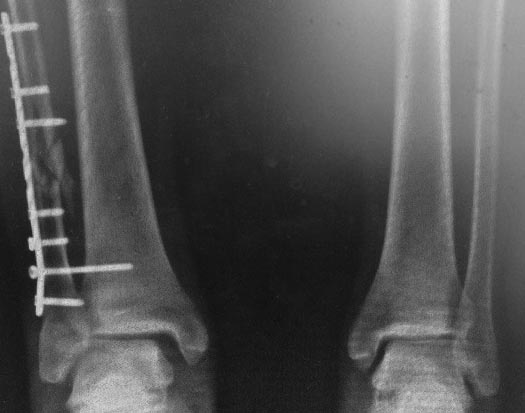

прямая проекция сейчас

до/после